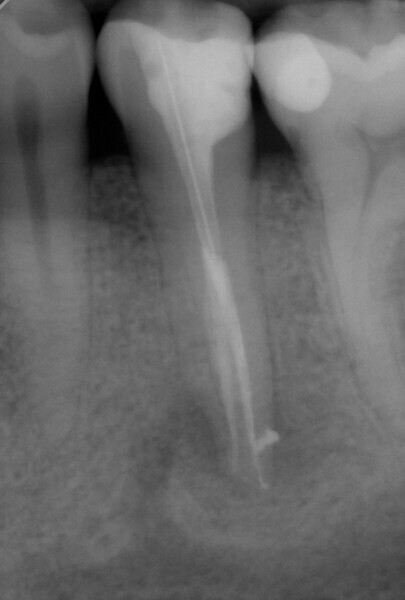

The treatment was performed in two appointments. The first appointment involved preparation, cleaning and interim medication with calcium hydroxide. After applying the dental dam to isolate the working field, the 25/0.12 HyFlex EDM Orifice Opener and the 10/0.05 HyFlex EDM Glidepath files were initially used to open the canal and create the glide path. The actual preparation was performed with 15/0.04 and 20/0.04 HyFlex CM files followed by the 25/~ HyFlex EDM OneFile (Fig. 4). During treatment, the canals were rinsed extensively with CanalPro sodium hypochlorite and EDTA and dried with the corresponding HyFlex paper points and the practical, flexible Surgitip endodontic aspirator tips (COLTENE) before application of the calcium hydroxide dressing (Fig. 5). Ultrasonic activation was also used to enhance the effect of the irrigation solutions.

Obturation and final restoration with a fibre post were performed at the second appointment. The radiograph confirmed that I had been able to treat both root canals along the entire length of the tooth (approximately 23 mm) with minimal loss of tooth structure and in the most conservative manner possible (Fig. 6).